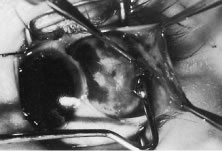

PYOGENIC GRANULOMA-CONJUNCTIVAL CYST

About 1 of every 100 strabismus operations will be complicated by the development of exuberant granulation tissue at the site of the conjunctival incision (Fig. 80). Tenon's capsule can protrude through the conjunctival incision and produce an exuberant granulation response. Granulation tissue is treated with frequent application of topical antibiotic-steroid drops. The granuloma usually will become pedunculated and drop off of the site. If the base is broad, the tissue is lifted with a forceps and removed with a scissors.

Fig. 80. Exuberant granulation tissue present 1 week after strabismus surgery.

Conjunctival cysts pose more difficult problems.61 These cysts usually form under the conjunctival surface, but some may be carried back with the recessed muscle and rest alongside the muscle or its new insertion (Fig. 81). Cysts occur more frequently after correction of strabismus in patients with strabismus following retinal detachment procedures or re-operations. Cysts do not respond to medical treatment and almost always require surgical excision. In these cases, the surgeon should attempt to remove the entire cyst structure or to marsupialize it if complete removal is impossible.

Fig. 81. A conjunctival cyst 3 months after strabismus surgery. These cysts will usually require surgical removal.